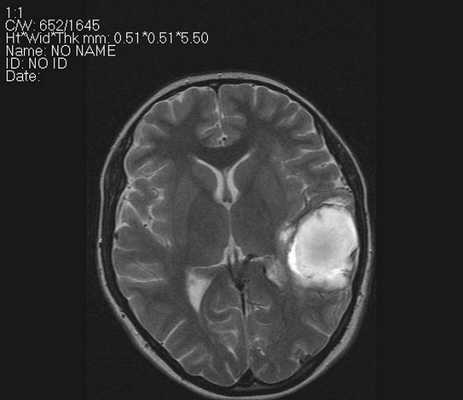

На PD/T2WI и FLAIR выглядит гиперинтенсивно. На PD/T2WI и FLAIR последовательностях возможно диагностировать до 80% инфарктов впервые 24 часа, но впервые 2-4 часа после инсульта изображение также может быть неоднозначным. На PD/T2WI и FLAIR продемонстрировано гиперинтенсивность в районе левой средней мозговой артерии. Обратите внимание на вовлечение в процесс лентиформного ядра и островковой доли. Область с гиперинтенсивным сигналом на PD/T2WI и FLAIR соответствует гиподенсивной области на КТ, что в свою очередь прямой признак гибели клеток мозга.